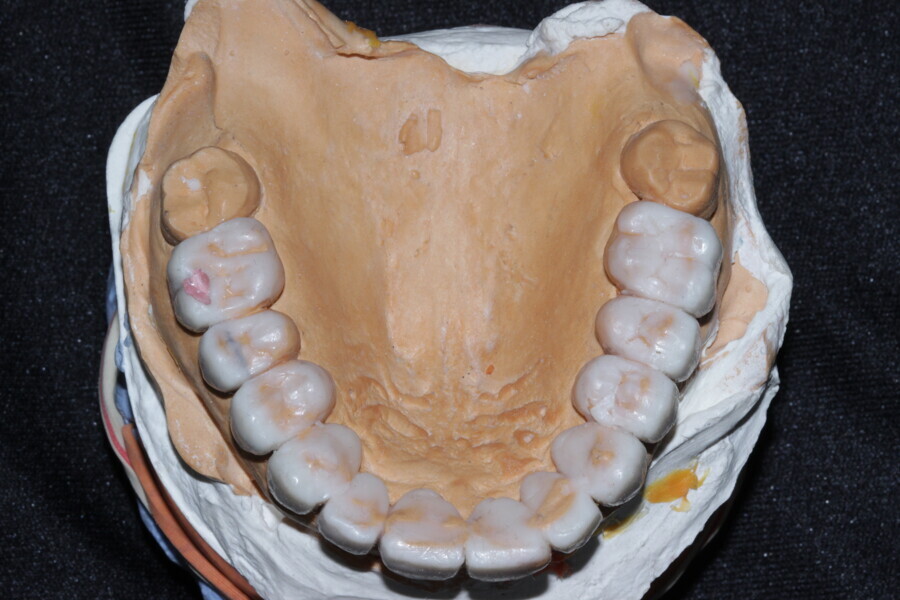

Figure 12 Diagnostic wax up as per digital smile designing planning

Figure 14 Diagnostic wax up as per digital smile designing planning

Figure 15 Diagnostic wax up as per digital smile designing planning